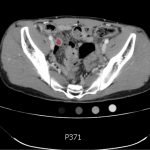

The CT abdomen/pelvis with intravenous contrast shows a dilated appendix (see red outline) with thickened, hyperenhancing wall (see blue outline) best visualized in the axial and coronal planes.